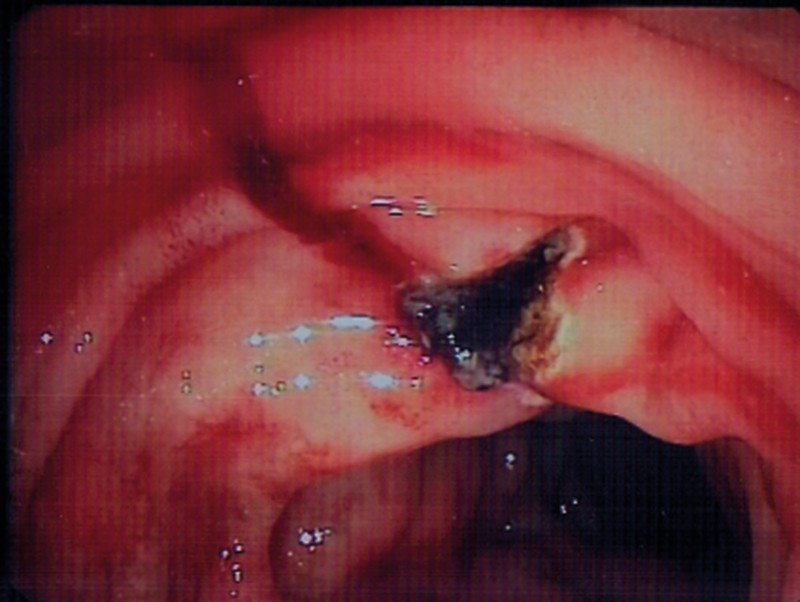

The patient was given two further bags of SAGMAN blood, and treatment was also started with tranexamic acid 1.5 g × 4 intravenously. A repeat gastroscopy on the afternoon of the same day showed continued fresh bleeding from the same area of the duodenum. Diluted epinephrine was again injected, which resulted in a diminution of bleeding. To obtain a better overview, an ERCP scope was used (optics to the side). It was thereby possible to see capillary bleeding from a point with no wound bed (Figure 1). Polidocanol 1 % was injected, total 4.5 ml at 0.5 ml per injection, and afterwards argon plasma coagulation (APC) was carefully applied to the point of bleeding until full haemostasis was achieved (Figure 2).

Figure 1  Persistent bleeding from a point (arrow) in the mucous membrane with no visible wound bed